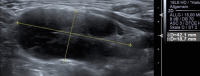

Abbildung 3: Lymphknotengröße. Bei diesem Lymphknoten aus dem Level 2 sind sowohl der Quer- als auch der Längsdurchmesser zu groß für diesen Halsabschnitt (quer max. 7–8 mm). „Diffuse large B-cell lymphoma“ (DLBCL).